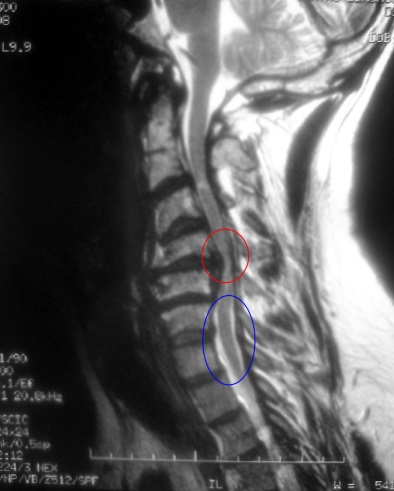

Posteriormente se realizarán pruebas de imagen que incluirán radiografías y Resonancia Magnética, que es la prueba más sensible y especifica. Es posible que también le soliciten estudios de conducción nerviosa.